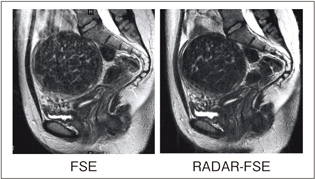

図5aはShoulderコイルによる肩関節の画像例で,通常のFSEと比較して呼吸によるモーションアーチファクトが低減されています。図5bのBodyコイルによる画像では,自由呼吸下のRADAR-FSEで,呼吸同期を併用した場合と同等の画像が得られています。

図5 RADARの各部位撮像例